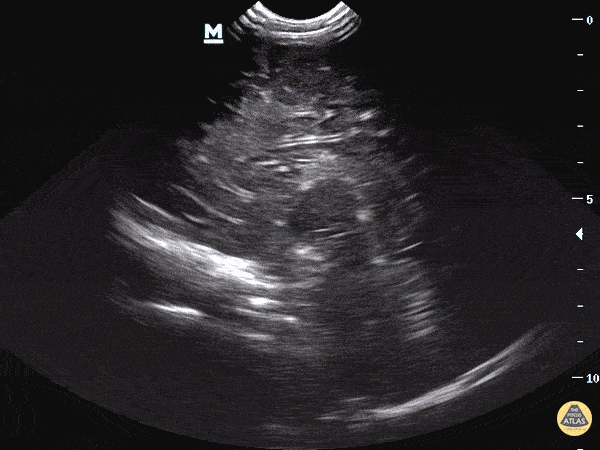

Clip 4: The sagittal plane has the indicator marker facing the anterior aspect of the face and the ultrasound beam is swept in either the left to right or right to left direction of the patient’s shoulders.